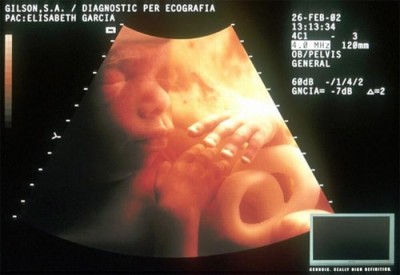

Siêu âm thai

Siêu âm là cách phổ biến nhất vì vừa an toàn vừa giúp bác sĩ theo dõi hình thái thai nhi. Khi thai đã đủ lớn và tư thế thuận lợi, bác sĩ có thể quan sát bộ phận sinh dục ngoài để suy đoán giới tính. Tuy nhiên, độ chính xác không chỉ phụ thuộc vào tay nghề mà còn phụ thuộc tuổi thai, vị trí thai nhi, lượng nước ối và cả việc thai có quay đúng góc hay không.

Chính vì vậy, siêu âm quá sớm thường dễ nhầm. Ở những tuần đầu, cấu trúc bộ phận sinh dục còn nhỏ, góc nhìn hạn chế và thai nhi liên tục xoay trở trong tử cung. Nếu mẹ bầu bám vào kết quả đoán sớm để kết luận chắc chắn, rủi ro nhầm lẫn là có thật. Mốc giữa thai kỳ, khi thai đã phát triển rõ hơn, thường cho hình ảnh đáng tin hơn nếu mục tiêu chỉ là quan sát hình thái.